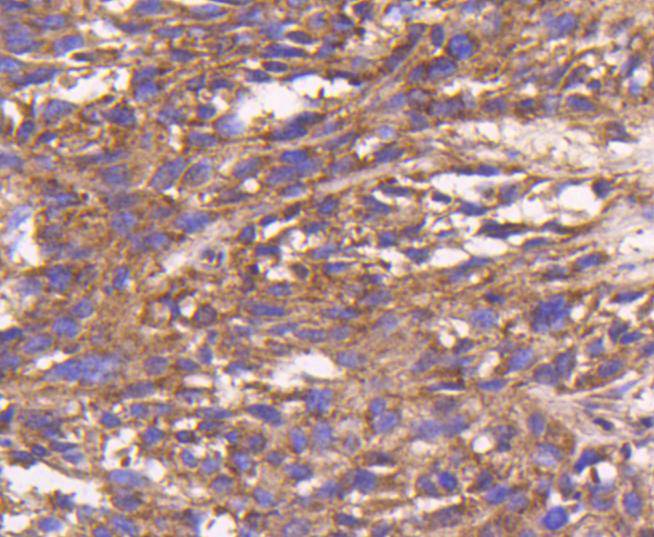

Immunohistochemical analysis of paraffin-embedded human liver cancer tissue using anti-Bax antibody. Counter stained with hematoxylin.